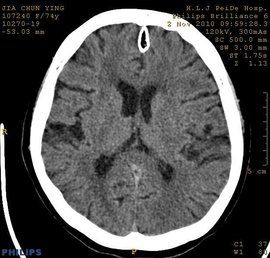

ct值CT值的計算:某物質的CT值等於該物質的衰減係數與水的衰減係數之差,再與水的衰減係數之比後乘以1000。即某物質CT值=1000×(u—u水)/ u水,,其單位名稱為HU(Hounsfield Unit),可見CT值不是一個絕對值,而是一個相對值.不同組織的CT值各異,各自在一定範圍內波動.骨骼的CT值最高,為1000HU,軟組織的CT值為20~70HU,水的CT值為0(±10)HU,脂肪的CT值為-50~-100以下,空氣的CT值為-1000HU.在實時螢光PCR中,ct值是指每個反應管內的螢光信號達到設定的閾值時所經歷的循環數